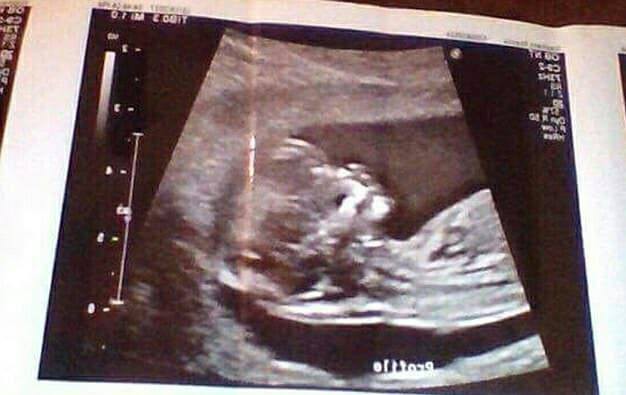

她指出:「我的寶寶每個月都像其他寶寶一樣,在肚裏慢慢成長,所以我所做的、跟寶寶健康損害無關。」